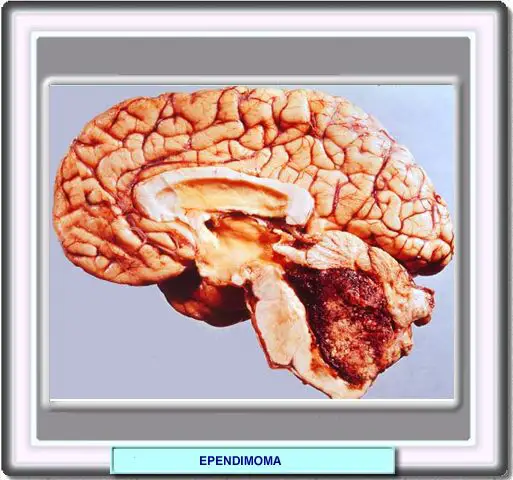

Gran tumor, focalmente hemorrágico, que llena y distiende el cuarto ventrículo. A pesar de su gran tamaño, el parénquima cerebral adyacente no ha sido invadido